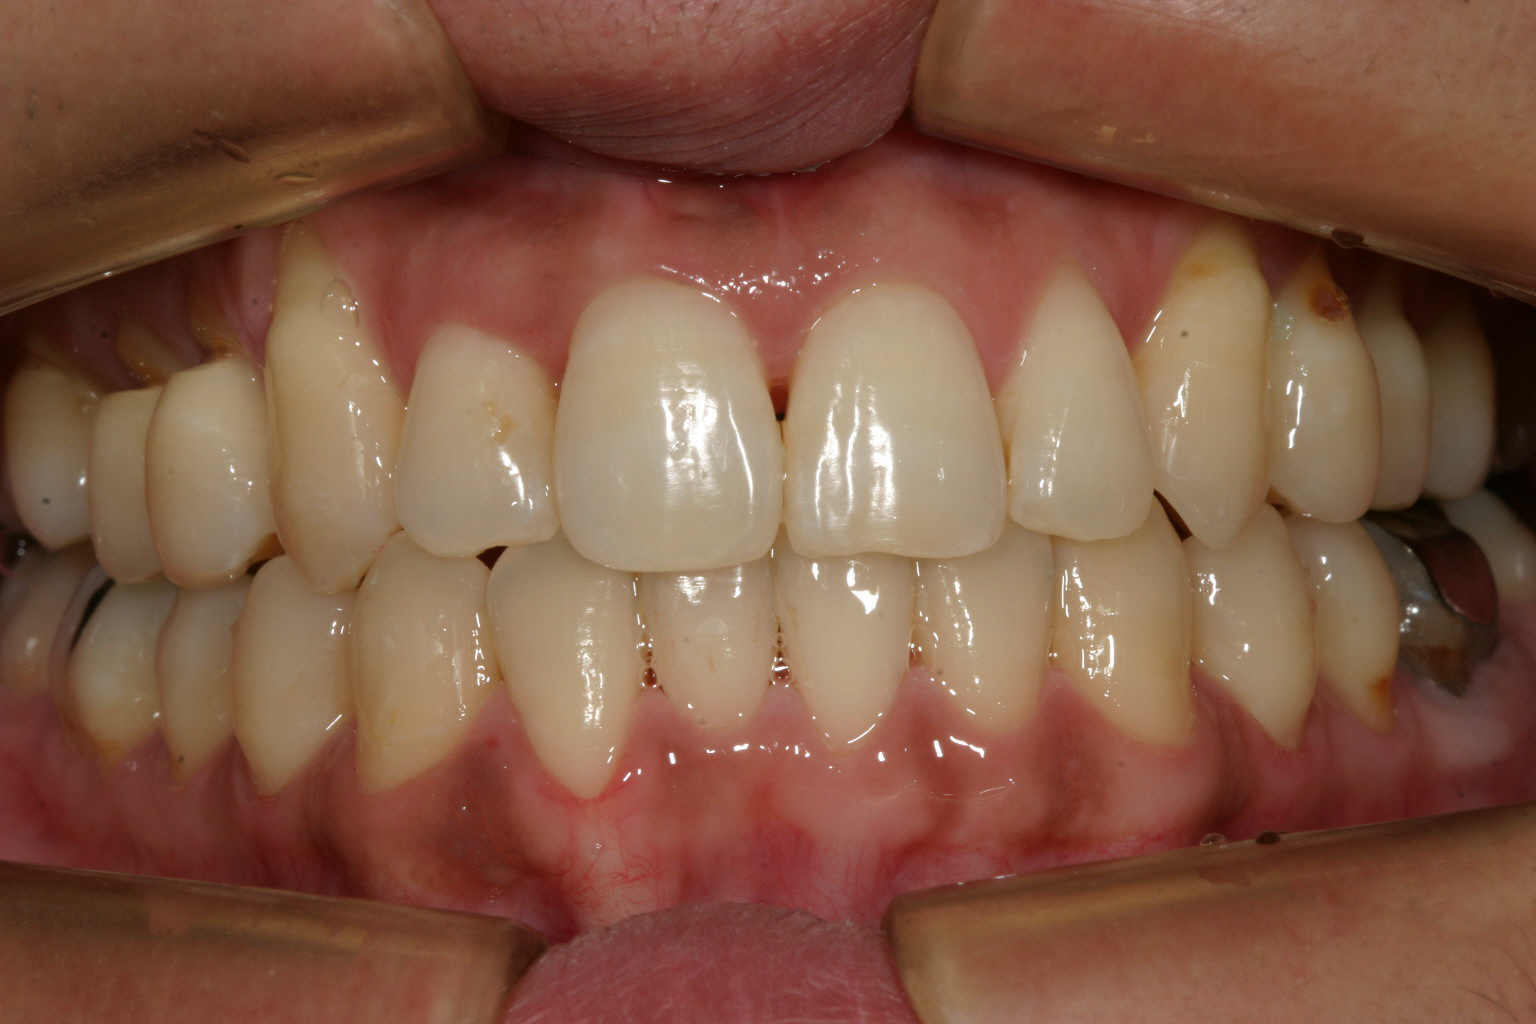

綺麗にアーチが改善しました。

下顎も叢生も取れ綺麗に改善してます。

側面観も申し分ないです。